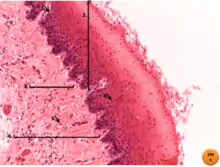

6. Tecido conjuntivo denso não modelado do esôfago

Já o tecido conjuntivo denso é adaptado para oferecer resistência e proteção aos tecidos. É formado pelos mesmos componentes encontrados no tecido conjuntivo frouxo, entretanto, existem menos células e uma clara predominância de fibras colágenas. Ele é menos flexível e mais resistente à tensão que o tecido conjuntivo frouxo.

Quando as fibras colágenas são organizadas em feixes sem uma orientação definida, o tecido chama-se denso não modelado. Neste tecido, as fibras formam uma trama tridimensional, o que lhes confere certa resistência às trações exercidas em qualquer direção. Este tipo de tecido é encontrado, por exemplo, na derme profunda da pele.